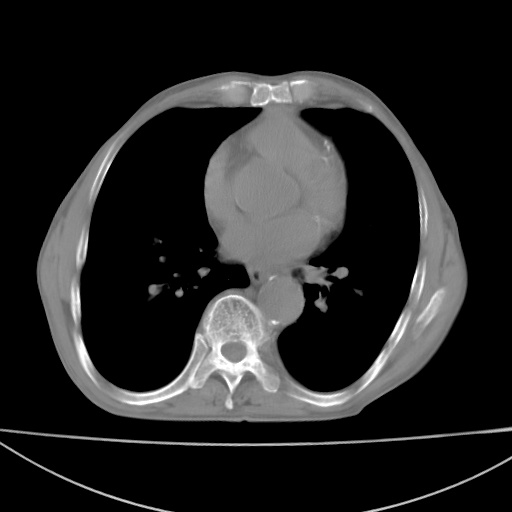

标题: CT13796:请会诊右上费病变!

患者男80岁,反复咳嗽多年,咳喘伴咯血1月

右上肺周围型肺癌伴肺门淋巴结转移.右上肺继发型肺结核.

右上肺周围型肺癌伴肺门淋巴结转移

右肺上叶占位性病变,考虑周围型肺癌,肺门淋巴结转移。要是能提供更多的临床资料就好了,以供鉴别诊断。

右肺尖周围型肺癌伴肺门淋巴结肿大

右肺上叶占位性病变,考虑周围型肺癌,肺门淋巴结转移。

右上肺周围型肺癌伴肺门、纵膈淋巴结转移

考虑为:右肺上叶肺癌伴阻塞性肺炎、右肺门及纵膈淋巴结转移。